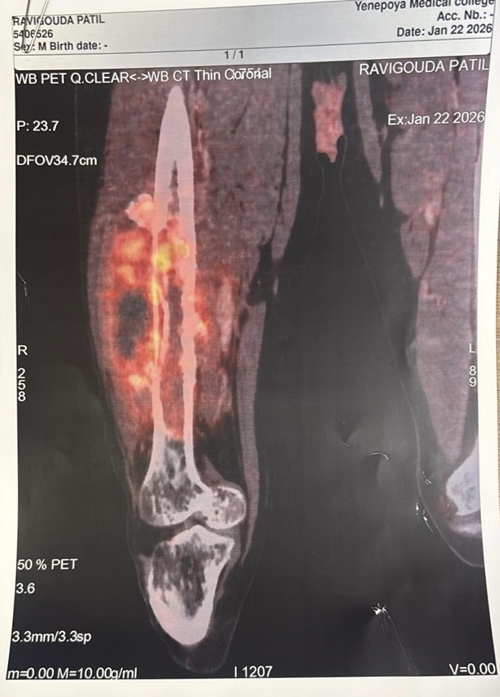

The patient, a resident of Haveri, presented with a tumour involving the right thigh bone and surrounding thigh muscles. After a thorough evaluation, he underwent four cycles of chemotherapy. Due to the extensive involvement of the thigh muscles by the tumour, the initial recommendation elsewhere was amputation of the entire leg.

During the 13-hour surgery, the entire length of the thigh bone along with the affected thigh muscles was removed. A titanium megaprosthesis was used to reconstruct the bone. Additionally, chest wall muscles, along with their blood vessels and nerves, were transferred using advanced micro neurovascular surgical techniques to reconstruct the thigh muscles and restore limb function.